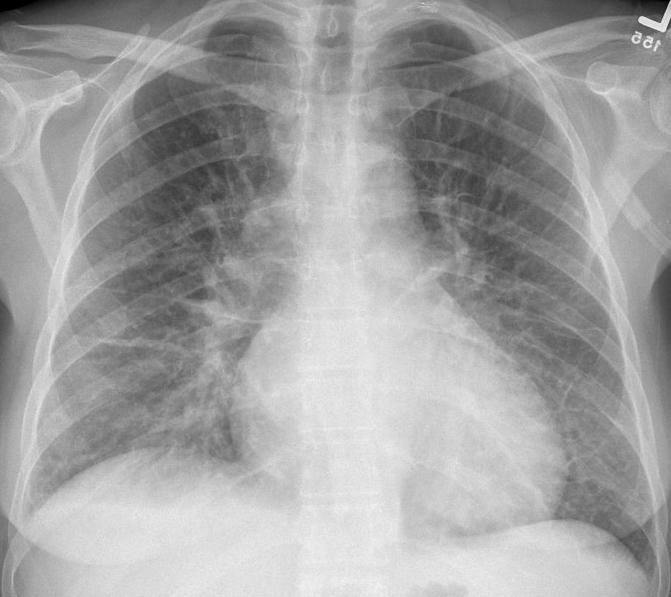

Gallery Cardiac Heart failure IPE 3 after

IPE 3 after